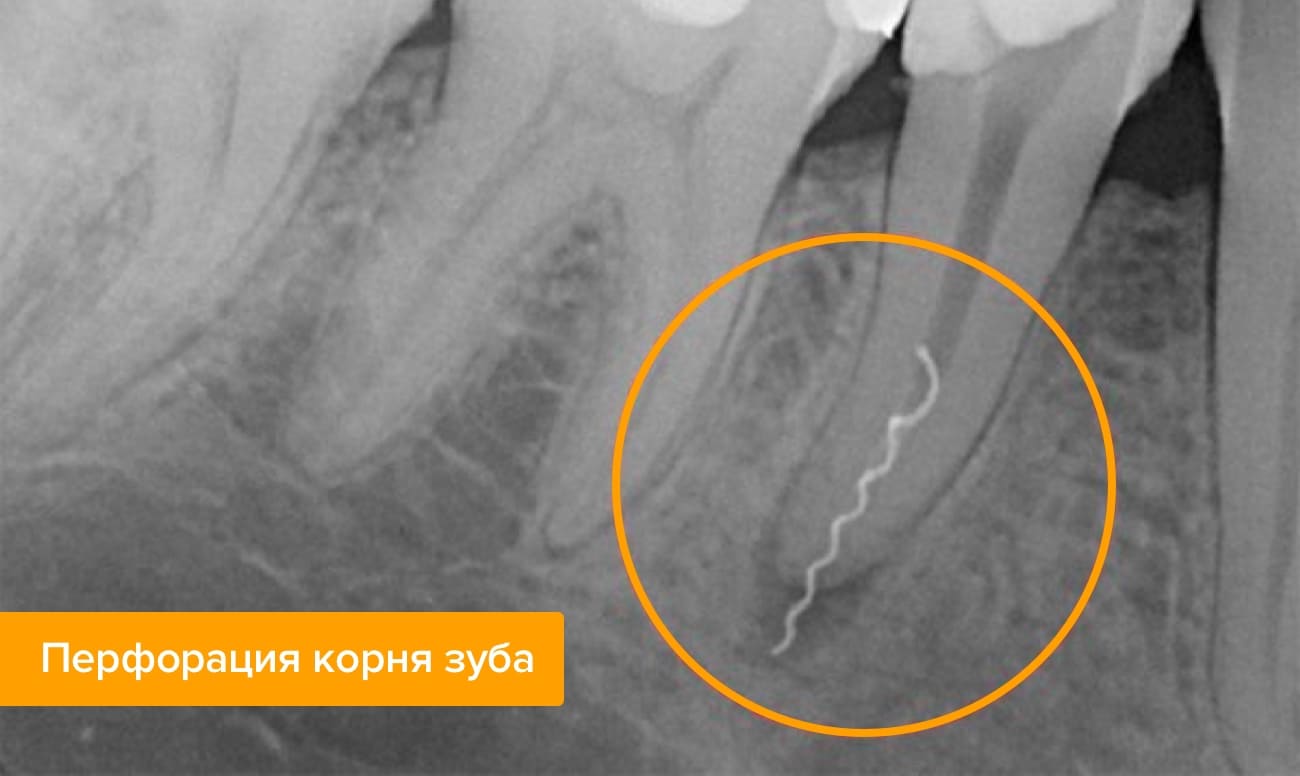

При обработке каналов произошла перфорация корня зуба

Перфорация — это прокол стенки корня при обработке канала эндодонтическим инструментом. Он опасен сам по себе: может привести к воспалению и нагноению тканей в области прокола, но также через отверстие в челюстную кость может попасть пломбировочный материал со всеми вытекающими последствиями. Из-за анестезии пациент не ощутит момент прокола, однако после окончания действия обезболивающих препаратов обязательно почувствует резкую боль. Она практически не снимается анальгетиками.

- перфорированная стенка зубного корня заделывается специальным материалом;